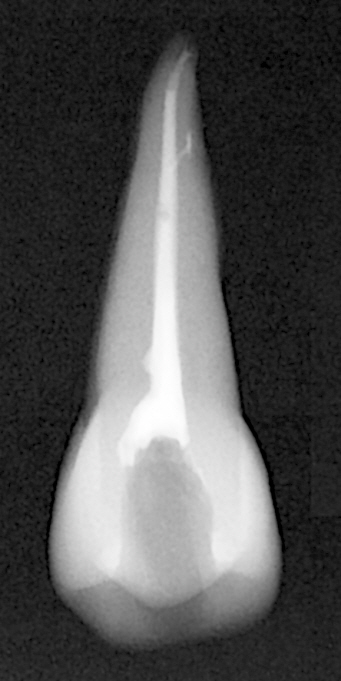

레진실러랑 CWT로 충전한 치아인데, 오늘 하면서도 역시나 근관 협-설측에 dead space가 보인다. 다행히 충전재로 채워지기는 했지만.

보면 파내려고 한 노력은 좀 보이는데, 미처 끝까지 다 접근하지 못했던 것 같다.

다행히 그래도 알파랑 콘덴서로 잘 compaction 한 덕분에 부근관도 필링이 된 걸 확인할 수 있기는 했다.

협측 근관이 짧아보이는 건 착시 같다 0.5mm까지 잘 들어갔다. 치아자체가 작고, 구개측이 실러때문에 더 길어보여서 그런 것 같다.

구개측 근관은 compaction하면서 실러가 근관공을 넘어갔다. 그렇게 퍼프가 생기면 3차원적으로 다 필링이 된 증거로 본다고 한다.